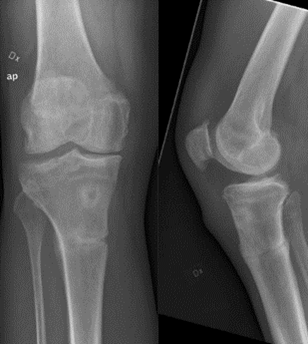

Röntgen inför proteskirurgi knä

• Viktigt i utredning för rätt vinkel av sågning osv. Kulan på bild är 30 mm

• Figursågning för att protesen ska passa perfekt. 6 grader valgus. Tibia rätvinkligt i frontalplan. Vi vill ha o-gradigt i HKA och efter som lårbenshalsen sticker ut lite snett vill vi ha lite valgus.

1. Korrekt benresektion enligt mallning/anatomi

2. Ligamentbalansering: dela strama strukturer så att ligamentbalansen blir korrekt både i flektion och i extension